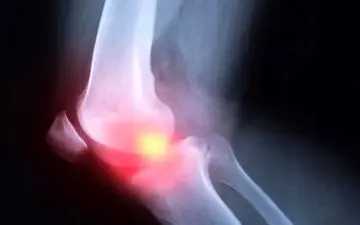

آرتروز در واقع آسیب به غضروفهای مفصلی زانو است که نقش اساسی در تسهیل حرکت استخوانهای ران و ساق دارند که پیشگیری مهم…

زانو، به عنوان یکی از بزرگترین و پیچیدهترین مفاصل بدن، نقش حیاتی در حرکت دارد و ازاینرو محافظت از آن باید در اولویت…